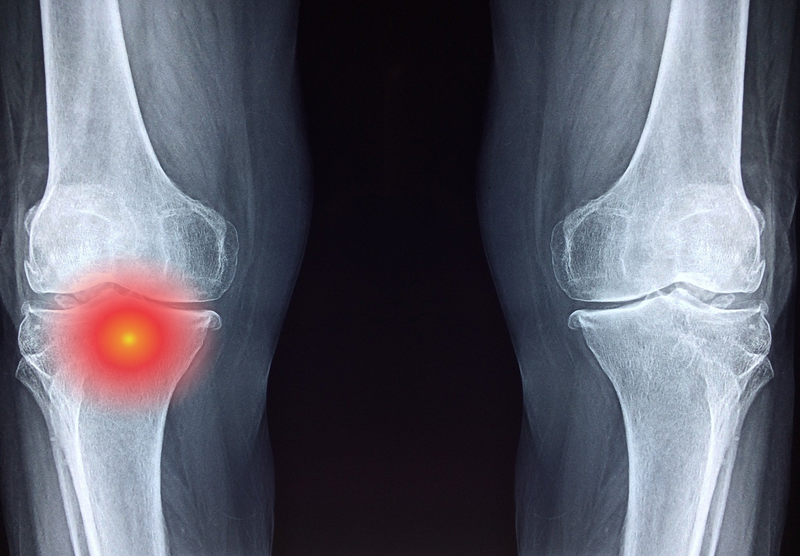

Bất cứ vị trí nào trên cơ thể cũng có nguy cơ mắc u xương ác tính, nhưng phổ biến nhất vẫn là những đốt xương dài khu vực cánh tay và chân, vòng quanh đầu gối và hai vai. Những khu vực như xương chậu, xương hàm hoặc xương sườn ít khi mắc phải các dạng u ác tính. Ngoài ra ở các đốt xương ngón tay hay ngón chân thường gặp phải dạng u xương lành tính hơn so với u ác tính.

Viêm tủy xương bán cấp: U xương ác tính ở dạng viêm tủy xương bán cấp hiếm khi xảy ra ở những bệnh nhân trẻ tuổi, nhưng không phải là không thể. Để chẩn đoán, bệnh nhân sẽ được chỉ định chụp X-quang. Khi mắc bệnh, người bệnh sẽ có những biểu hiện lâm sàng là sốt cao, tốc độ máu lắng tăng.

Di căn xương thứ phát: Đây là dạng u xương ác tính tương đối nặng. Bệnh nhân sẽ nhận thấy những triệu chứng đặc trưng bao gồm đau nhức nghiêm trọng ở khớp xương, dây thần kinh bị đứt quãng, gãy xương do bệnh lý. Khả năng di căn xương thứ phát đến các cơ quan như phổi, ngực, hoặc tuyến tiền liệt là rất cao.

/https://cms-prod.s3-sgn09.fptcloud.com/dau_hieu_sarcoma_xuong_u_xuong_ac_tinh_o_tre_em_va_thanh_thieu_nien_3_c94c906d3d.jpg) Hình ảnh chụp X-quang viêm tủy xương cấp

Hình ảnh chụp X-quang viêm tủy xương cấp Phần lớn, những bệnh nhân Sarcoma xương đều cần thực hiện phẫu thuật bảo tồn (Limb – Sparing). Bằng phương pháp này, bác sĩ sẽ dễ dàng loại bỏ đi khối u ác tính, cùng những vùng xương đã bị khối u xâm lớn. Với những trường hợp u xương ác tính thể nặng hoặc đã di căn đến các cơ quan khác, bệnh nhân bắt buộc phải cắt bỏ toàn bộ phần khớp gối, sau đó, thay thế bằng xương kim loại nhân tạo.